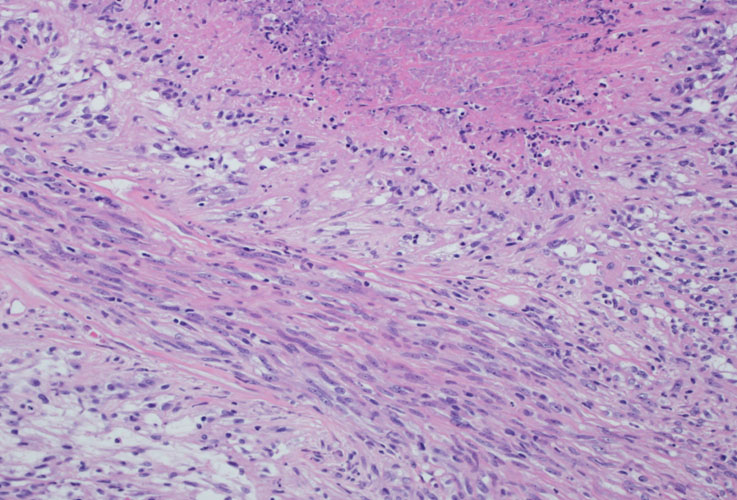

| Pathologist 16 | Tubulocystic RCC | Not typical |

sarcomatoid change |

| Pathologist 19 | Other | Not typical |

tubulocystic RCC with poorly differentiated focus? |